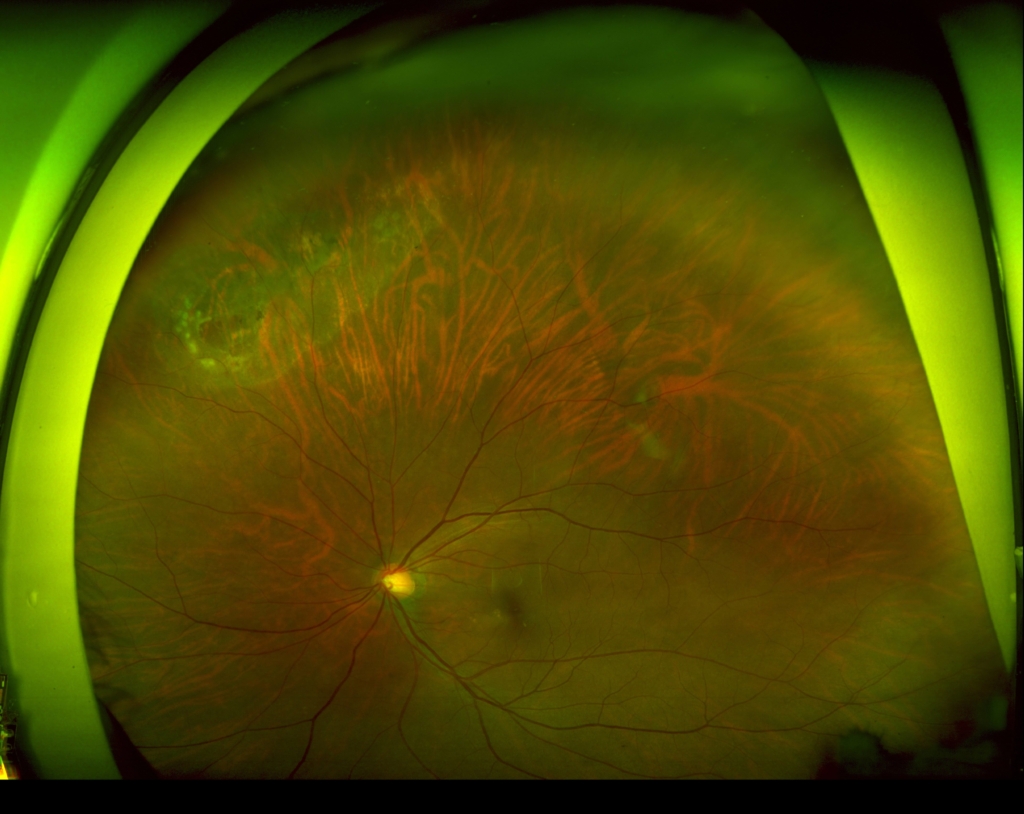

60歳 女性

主訴 10日前から飛蚊症、2日前から視野欠損を自覚

視力 右眼 0.6(1.2×-0.75)

鼻上側に剥離が剥離があり、格子状変性の耳側縁に馬蹄形裂孔がみられる。